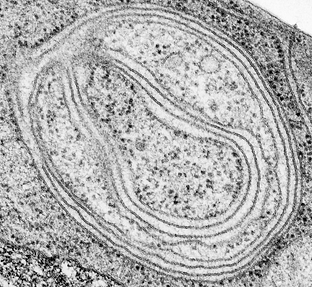

(A picture of an autophagosome taken with an electron microscope, courtesy Wikimedia Commons)

At the conceptual level, autophagy is triggered by autophagosomes, cell organelles that serve as containers for food and/or waste. The larger and more numerous the autophagosomes, the more prone the cell is to begin consuming itself in times of peril. The tricky part about autophagy is that it isn’t clear whether cells would benefit more from an increase or decrease in autophagy. Much of this debate focuses on cancer. For instance, autophagy is responsible for the removal of damaged proteins and organelles; therefore, autophagy can actually help suppress tumors. On the other hand, cancerous cells also use autophagy to keep themselves alive when they would have otherwise died.